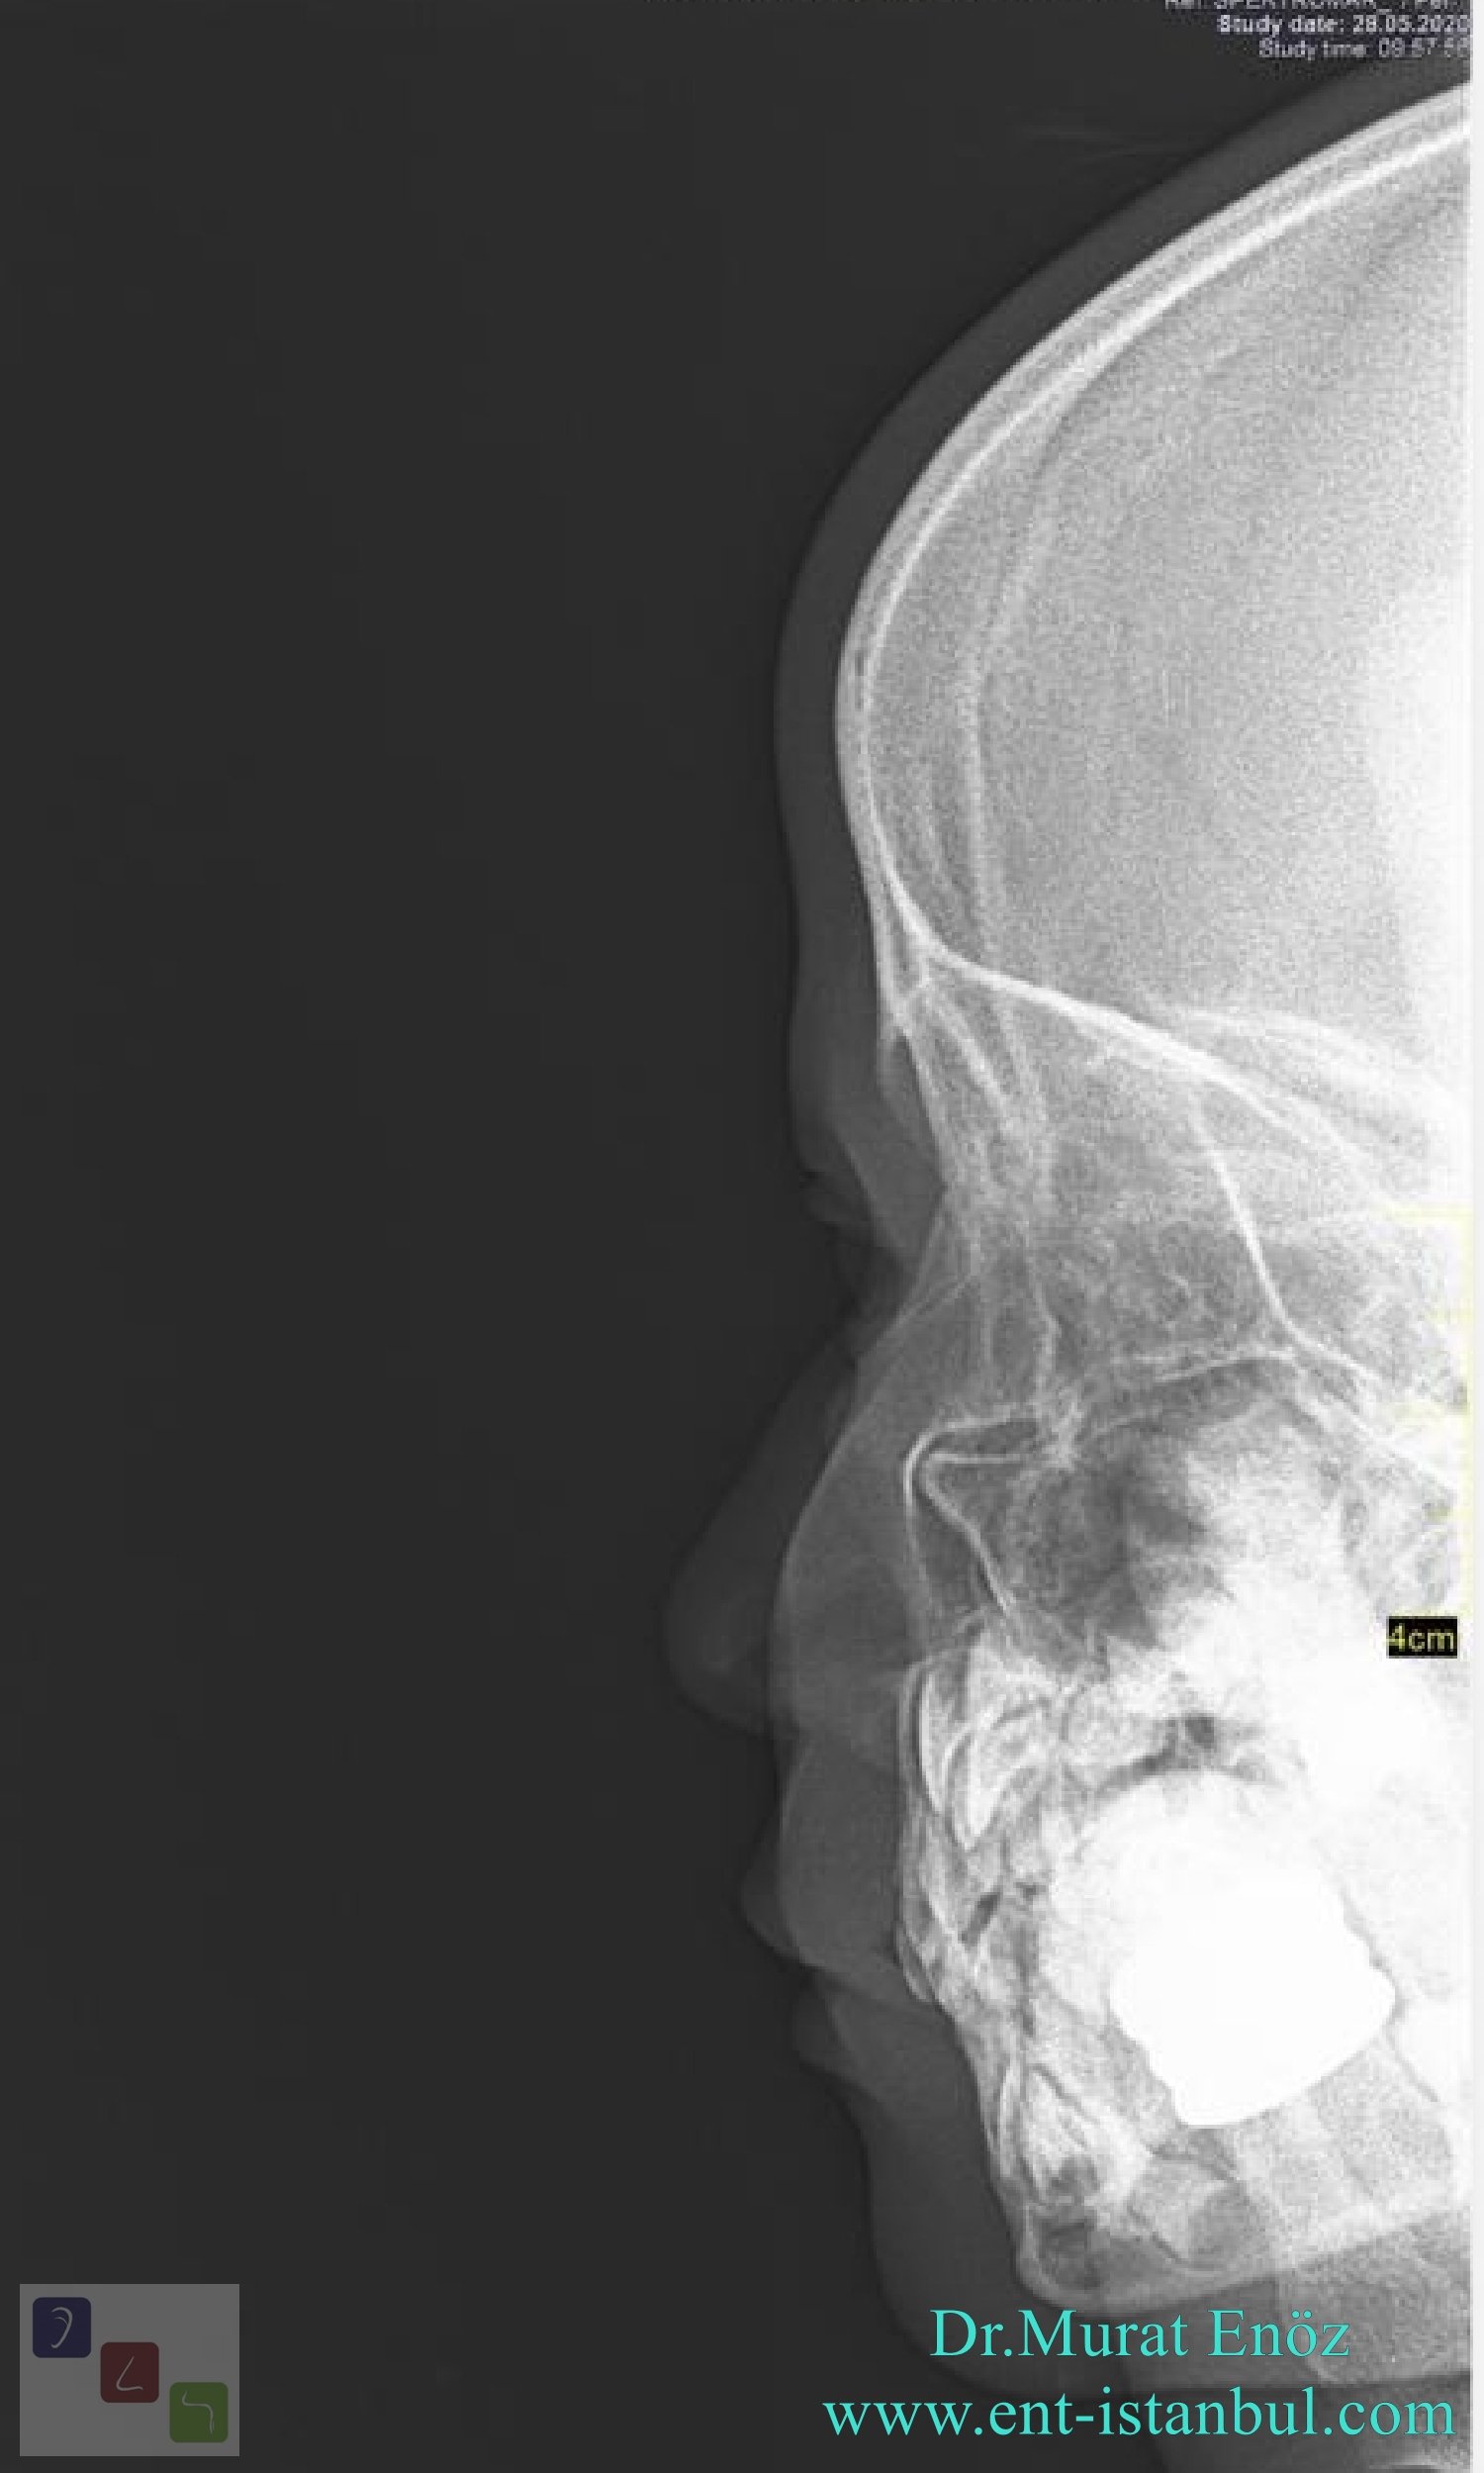

From www.ent-istanbul.com

Nasal Fractures Causes, Symptoms, Diagnosis, Treatment Nose Fracture X-Ray There is also an associated fracture of the anterior nasal spine (red. Evaluate nasal bone and septal fractures appropriately. Nasal trauma is a common presentation to the emergency department. In cases of facial trauma, nasal fractures account for approximately 40 percent of bone injuries. injuries to the nose are relatively common; It can range from minor injuries and bleeds. Nose Fracture X-Ray.